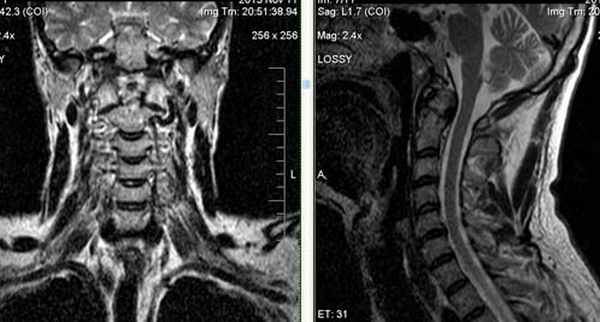

Аномалия кранио-вертебрального перехода: ассимиляция С1, затылочной кости, зубовидного отростка С2 позвонка; базиллярная импрессия. Ротационное смещение С1 позвонка, гипертрофия боковых масс тела С1 позвонка. Стеноз большого затылочного отверстия. Очаговая миелопатия на уровне С2 позвонка.

Сращение правых отделов боковых масс атланта и основания затылочной кости (синостоз правого атланто-окципитального сочленения).